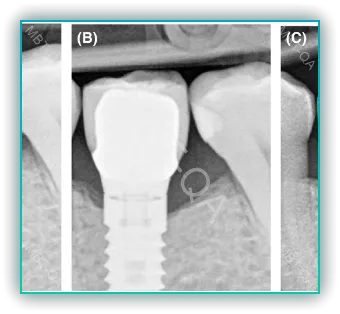

앞니 임플란트를 실시할 때, 주변 뼈 소실 문제는 중요한 고려 사항입니다. 임플란트 주변의 뼈가 소실되면 임플란트의 안정성과 지속성에 영향을 미칠 수 있으며, 심미적인 문제도 발생할 수 있습니다.

임플란트 주변 뼈 소실의 원인은 다양합니다. 치아를 뽑게 되면, 해당 부위의 뼈가 자연스럽게 흡수되기 시작합니다. 이러한 뼈 소실은 임플란트가 제대로 고정되지 않는 문제를 유발할 수 있습니다. 또한, 임플란트 식립 후에도 뼈의 소실이 계속될 수 있으며, 이는 임플란트의 장기적인 성공에 영향을 줄 수 있습니다.

- 치아 추출 후 즉시 임플란트 식립: 가능한 한 치아를 뽑은 직후에 임플란트를 식립함으로써 뼈 소실을 최소화할 수 있습니다.

- 뼈 이식 수술: 뼈의 양이 부족한 경우 뼈 이식을 통해 임플란트를 지지할 수 있는 충분한 뼈를 확보하는 것이 중요합니다.

- 적절한 임플란트 위치와 각도: 임플란트를 식립할 때, 올바른 위치와 각도를 선택하는 것이 중요합니다. 이는 뼈와 임플란트의 안정적인 결합을 돕고, 뼈 소실을 방지하는 데 중요한 역할을 합니다.